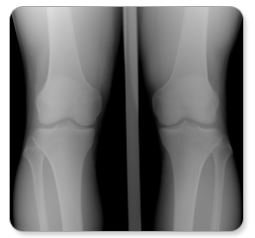

난 슬개골연골연화증 때문에 엄청 고생했는데

특히 내가 고생했던 슬개골연골연화증은

20~30대에 발병이 더 많아지고 있어